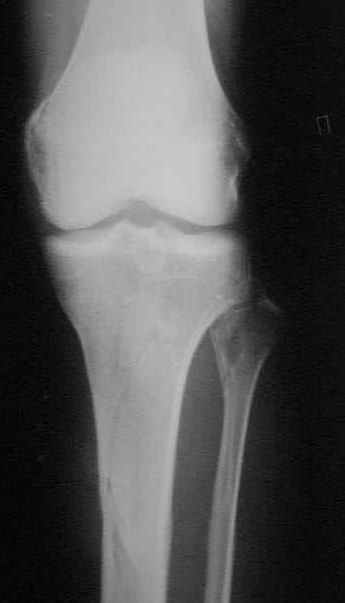

Открытый (2 В Каплан) многооскольчатый перелом левого бедра. Перелом межмыщелкового возвышения большеберцовой кости без смещения слева. Открытый (1 А Каплан) перелом с/3 -н/3 костей правой голени, перелом пяточной кости справа.На седьмые сутки выполнены операции:1. ЗИМО (статически, Chm-CHARFIX) левого бедра. 2. Остеосинтез стержневым аппаратом костей правой голени и пяточной кости. См. r-gr.На сегодня аппарат демонтирован, больной ходит с ограниченной нагрузкой.Смущает стояние отломков в верхней трети бедра (как то не задумались при планировании операции о реконструктивном или гамме штифте ) хватит ли этих двух винтов для стабильности?С Уважением Владимир Бахарев.

Длина проксимального отломка тут достаточна для использования любого диафизарного гвоздя, так что в этом отношении как раз все в порядке. Запас прочности, однако, тут для ранней полной нагрузки недостаточен, и даже с реконструкционным было бы немногим больше - дистальные винты те же 4,5 мм, а они у гвоздей ChM довольно хлипкие. Так что с нагрузкой тут лучше не спешить до уверенных признаков пластики на снимках.

Видна заметная наружная ротация центрального отломка. Если это не случайно сделали снимок, не выведя колено в нейтральное положение, то это типичное смещение, если делать синтез на тракционном столе с тазовой подставкой и промежностным упором. Стоило бы сделать снимок обоих тазобедренных суставов при одинаково уложенных коленных. Для этой же цели можно сделать и снимок в сгибании 90 градусов коленых и тазобедренных суставов, будет прямо видно

антеверсию шеек. Спасибо за презентацию непростого пациента.